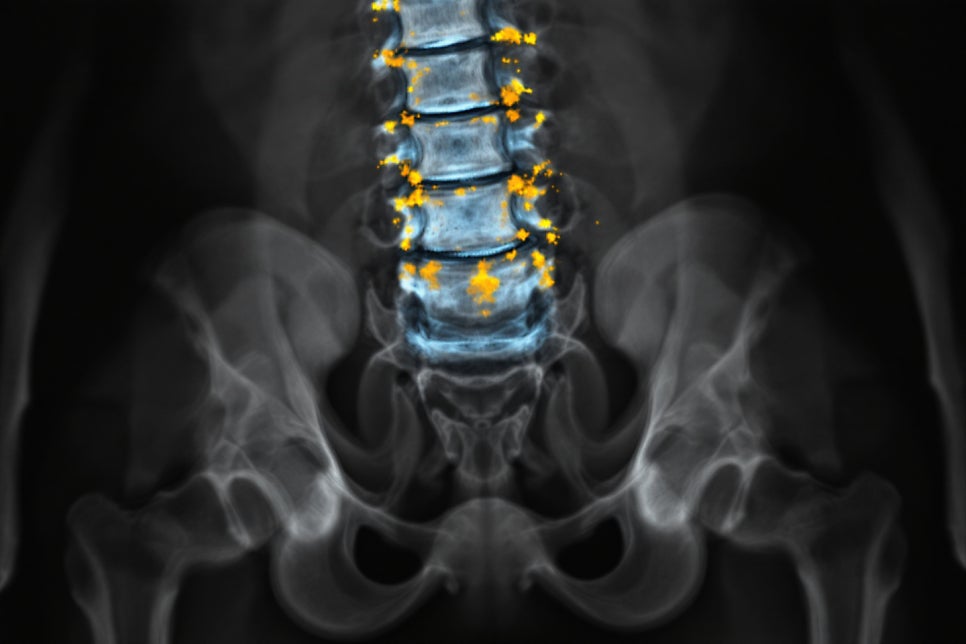

척추형

척추와 천장관절에 발생하며, 이는 류마티스관절염과 구별되는 특징을 보입니다.

약 20–30%에 해당하며, 때로는 강직성 척추염과 구분하기 어려운 경우도 있어요. 차이점은 양측보다는 편측으로 나타나는 경우가 많다는 것이고, 가동성 제한은 심하지 않다는 점입니다.